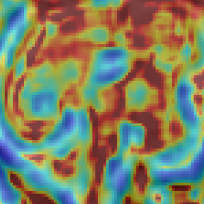

We additionally perform preliminary experiments towards integrating network-based SR components more tightly with an SVR pipeline by investigating the ability of the network to upsample LR voxel intensities that result from an initial volume reconstruction iteration. Successful integration of an iterative (learning-based) SR and volume reconstruction loop will facilitate the well understood mutual benefits of reduced-motion SR input and improved input fidelity for the motion correction task. Qualitative comparison of () LR volume-reconstructed input and resulting upsampled results are found in Fig.3. The benefit of learning the upsampling with modality specific data can be observed to manifest as sharper edge gradients and improved high frequency signal components. The visual quality gap between the baselines and our method can be seen to widen as the prior information required to successfully upsample at larger factors make the task more challenging.

Volume Reconstruction Improvement: In our third experiment we evaluate SVR performance using LR input stacks, upsampled by the considered strategies, before initiating the volume reconstruction task. We additionally perform SVR reconstruction with original HR imagery to provide the “ground-truth” reference brain volumes. Employing the three quality metrics, introduced previously, we evaluate how well super-resolved LR stack reconstructions correspond to the reconstructions due to original high, in-plane, resolution imagery. Table 1 reports PSNR, SSIM and cross-correlation metrics for volume comparison (SR strategy with respect to “ground-truth” volume) for the patients that define the MRI stack test set. Super-resolving the LR input data with the proposed learning based approach can be observed to facilitate reconstruction improvement, across the investigated metrics. Visual evidence supporting this claim is found in Fig. 4 (best viewed in color). Fig. 4 displays 2D slices of patient fetal brain reconstructions resulting from the original HR input-imagery (far left) and identically spatially-located slices (a) resulting from (b) LR imagery (half the in-plane resolution), (c-d) input using naïve up-sampling strategies and (e) our 3D MRI CNN upsampling. Corresponding Structural Dissimilarity (DSSIM) error heatmaps (second row) provide improved visual spatial congruence between HR ground-truth and our method, supporting the claim that utilizing sensor specific priors is of marked benefit for the task of MRI fetal brain reconstruction from LR imagery.